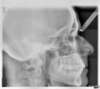

Les radios avant le traitement